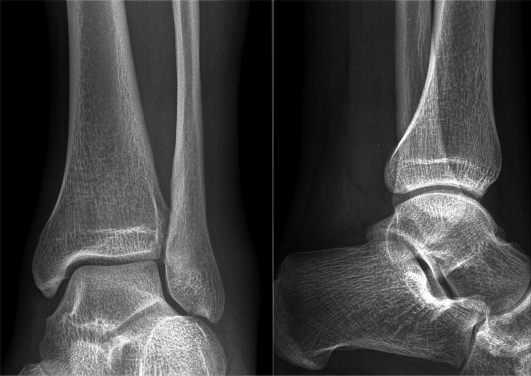

На 1 стадии больного может ничего не беспокоить. Окончательный диагноз выносится на основании рентгенологического исследования пораженной области. Оно способно выявить сужение суставной щели, деформацию, подвывихи, наличие остеофитов. Все эти признаки можно определить на 2 или 3 стадии болезни. Нужно помнить, что при появлении первых симптомов заболевания требуется обратиться к врачу. Известно, что остеоартроз имеет склонность к прогрессированию. При отсутствии адекватной терапии первая степень может перейти во вторую, а затем — в третью. Исход остеоартроза — это разрушение голеностопного сустава и формирование анкилоза (неподвижности). Все это свидетельствует о том, что лечебные мероприятия нужно проводить как можно раньше.

Даже не всегда на рентгенограмме видно, что артроз начал разрушать голеностоп. Более подробный результат можно получить от МРТ, которое наглядно покажет, что суставная щель немного сужена и появились мельчайшие остеофиты.

Диагностика соответствующей патологии голеностопа не является сложной. На фоне характерных жалоб пациента на боль после физической нагрузки и ограничение движений врач дополнительно назначает рентгенографию пораженного сустава.

На снимках фиксируется уменьшение внутрисуставной щели, что подтверждает диагноз. В сомнительных случаях дополнительно может использоваться магнитно-резонансная томография, которая показывает состояние хряща.